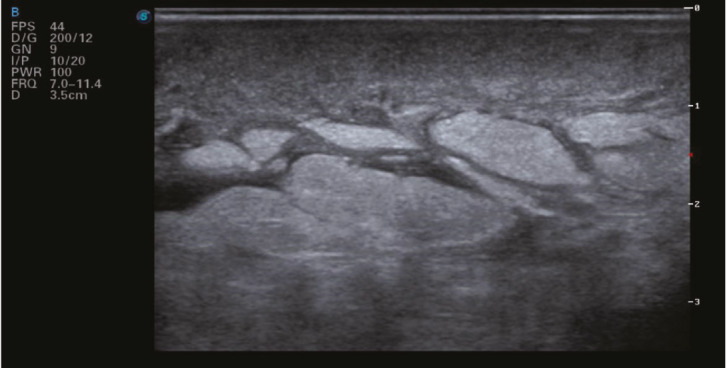

Breast lymphedema is a common but underdiagnosed condition that affects the quality of life of patients. It may be caused by any pathology that disrupts lymphatic drainage in the breast. We present the case of a woman with axillary lymph node tuberculous infection with breast edema, clinically and radiographically indistinguishable from tuberculous mastitis. After six months of comprehensive antituberculosis pharmacological treatment, the persistence of breast edema required repeating diagnostic tests searching for malignancy, all of which were negative. Rehabilitation treatment with complex physical therapy improved the patient's clinical and symptomatic condition. Clinical suspicion of secondary lymphedema is crucial to avoid unnecessary diagnostic procedures and ensure adequate and timely treatment.

Abstract Image